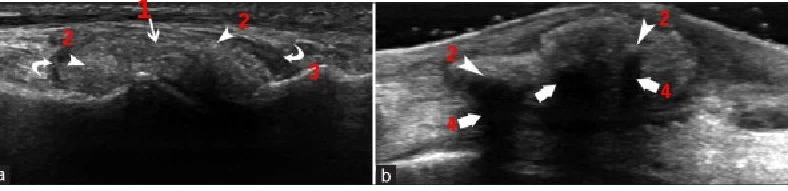

Для раннего подтверждения диагноза подагры используют УЗИ суставов и прилежащих тканей. Метод выявляет как признаки артрита, так и тофусы в окружающих участках. Узи в практике используют и урологи для обследования почек у пациента с подагрой, подозрении на мочекаменную болезнь и задержку мочи.

Узи суставов – быстрая и безболезненная диагностика подагры при остром эпизоде, так и при узловых образованиях кожи пальцев и ступней между приступами. При наличии любого артрита проводится пункция под контролем ультразвука, во-первых, с лечебной целью для удаления воспалительного содержимого, а во-вторых, с диагностической целью. Опыт наших врачей позволяет легко использовать УЗИ для отслеживания динамики лечения подагрического артрита, ведь оно не несет лучевой нагрузки и может исследовать костные соединения в любой проекции.